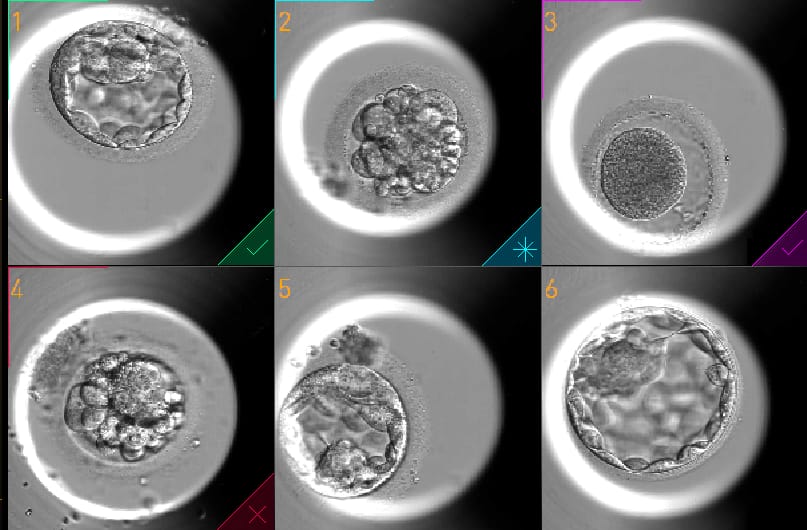

Um dos desafios dos tratamentos de reprodução assistida é garantir a implantação do embrião no útero da futura mãe para que a gravidez aconteça e se desenvolva de forma saudável, evitando a repetição de ciclos de Fertilização in Vitro, que costumam ter um custo emocional e financeiro para os pacientes que buscam ajuda especializada para ter filhos. Para otimizar esse processo, o Cenafert, que integra o Grupo Huntington, acaba de implantar, de modo pioneiro em Salvador, uma incubadora de última geração que permite monitorar o desenvolvimento do embrião em tempo real e sem manipulação externa. Trata-se do EmbryoScope® Plus, equipamento de alta tecnologia que funciona com um sistema de vídeo time-lapse capaz de gerar imagens a cada 10 minutos, permitindo avaliar com precisão padrões do crescimento embrionário, 24 horas por dia, sete dias por semana.

No método tradicional, os embriões precisavam ser retirados do seu cultivo na incubadora para avaliação através de um microscópio externo. Com a incubadora dotada do sistema de vídeo time-lapse e integrada à inteligência artificial Maia, os embriões não precisam ser manipulados fora do seu ambiente durante todo o período de cultivo laboratorial. “Essa tecnologia permite que o monitoramento do desenvolvimento embrionário e a seleção dos melhores embriões sejam realizados de forma mais assertiva e segura, sem demandar nenhuma manipulação externa “, afirma Janaina Mendes Maciel.

Desenvolvida pela Grupo Huntington ao longo de seis anos, a MAIA é uma Inteligência Artificial, que analisa imagens de Fertilização in Vitro (FIV). Com a capacidade de monitorar até 240 embriões simultaneamente, a tecnologia oferece análises precisas que auxiliam o embriologista na escolha do melhor embrião.